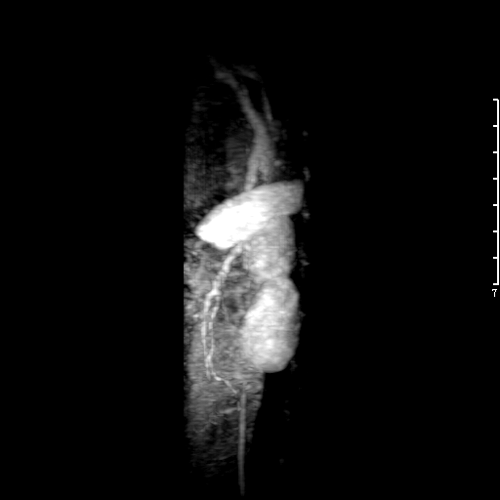

聚多巴氨基酸的兒茶酚基與三價鐵離子形成穩定配位結構,在水溶液中自組裝成螯合三價鐵的聚氨基酸膠束,成功實現磁共振成像(MRI),比商用釓試劑具有更好的弛豫速率(r1=5.6mM?1s?1)。該膠束直接應用于小鼠和兔子體內,成功實現了磁共振血管造影,得到靜脈和動脈的清晰三維圖像。